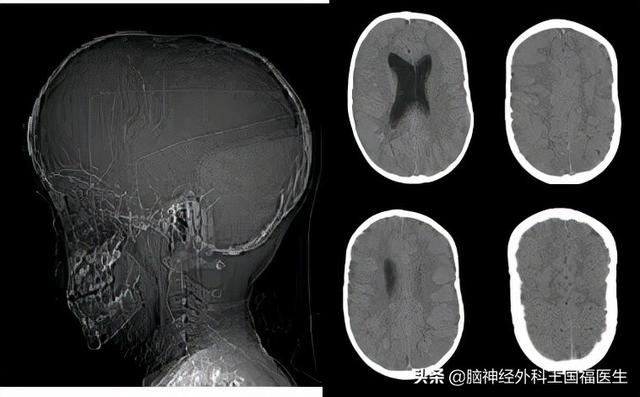

儿童神经外科医生诊查后,发觉小刚的头型有异常,明显是一个颅缝早闭的头型,马上安排拍个头颅平片进行确认。

片子中发现小刚的颅骨布满指压痕,确认肯定存在颅骨对脑组织的压迫,可以确定就是颅缝早闭。

小刚的头型就已发生了明显的异常,并且在颅骨上留下了明显脑组织受压的痕迹,这种压迫有很大可能就是导致小刚癫痫发作的原因。

在患儿一岁时曾经因为“中耳炎”做过一次头颅CT检查,从这张片子分析,出现冠状缝和矢状缝,至少在能看到的部分层面上,是没有闭合的。

而在患儿4岁时,复查耳部CT,则可以看出头颅的外形已经开始改变,在颅骨内板上已经出现了对脑组织的压迫征象,这些像连续小锯齿一样的边缘,就是脑组织在坚硬的颅骨内板上压出来的痕迹。

而现在呢,明显的头颅已经呈前后径明显拉长的舟状颅,颅骨内板上已经布满了脑组织压迫所出现的压痕。